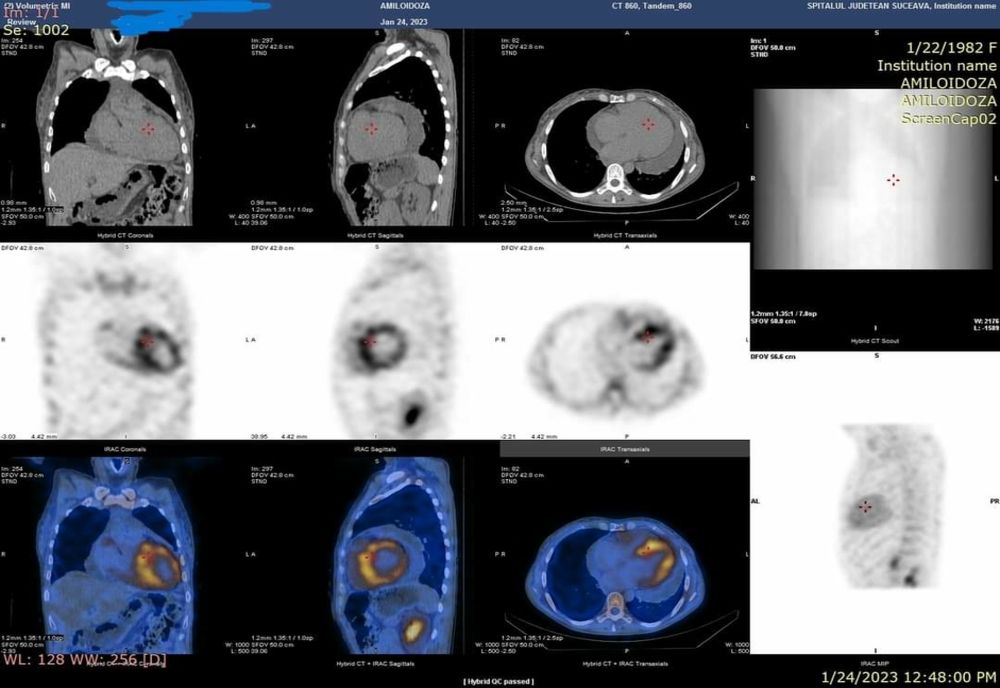

Recent, in Laboratorul de Medicina Nucleara al SJUSV in cadrul Centrului de diagnosticare si tratament al Amiloidozei coordonat de dr. Neagu Daniela medic primar neurolog impreuna cu dr Rusu Ramona medic primar cardiolog, a fost investigat un caz de amiloidoza ereditara prin scintigrafie cu Tc99m-difosfonat. Fixarea radiofarmaceuticului in aria de proiectie cardiaca (scintigrafia corp intreg) similara fixarii costale sau peste fixarea costala este diagnostica pentru acest tip de patologie. Pentru reducerea rezultatelor scintigrafice fals pozitive, se poate efectua suplimentar achizitie SPECT/CT. Astfel se diferentiaza daca fixarea este la nivel miocardic, circulant sau extracardiac.